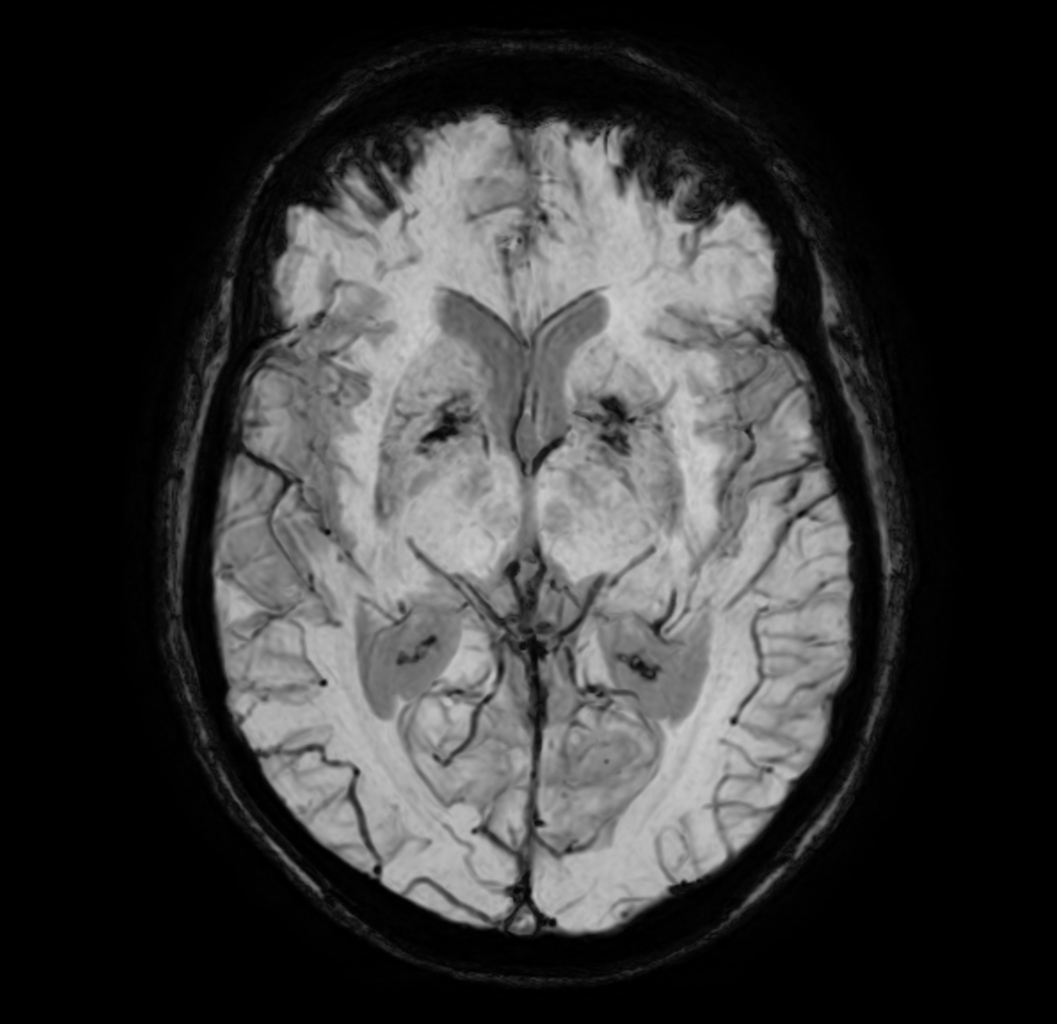

SWIp (minIP)